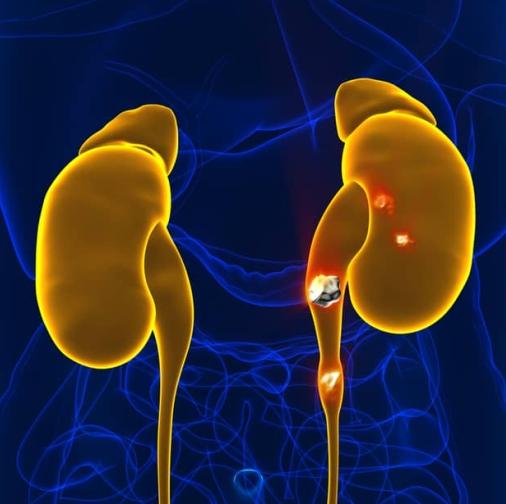

Piedras en el riñón y vejiga

Cálculos renales

Vías urinarias del hombre y la mujer

- Piedras en los riñones

- Tumores de riñón, vejiga, próstata y testículo